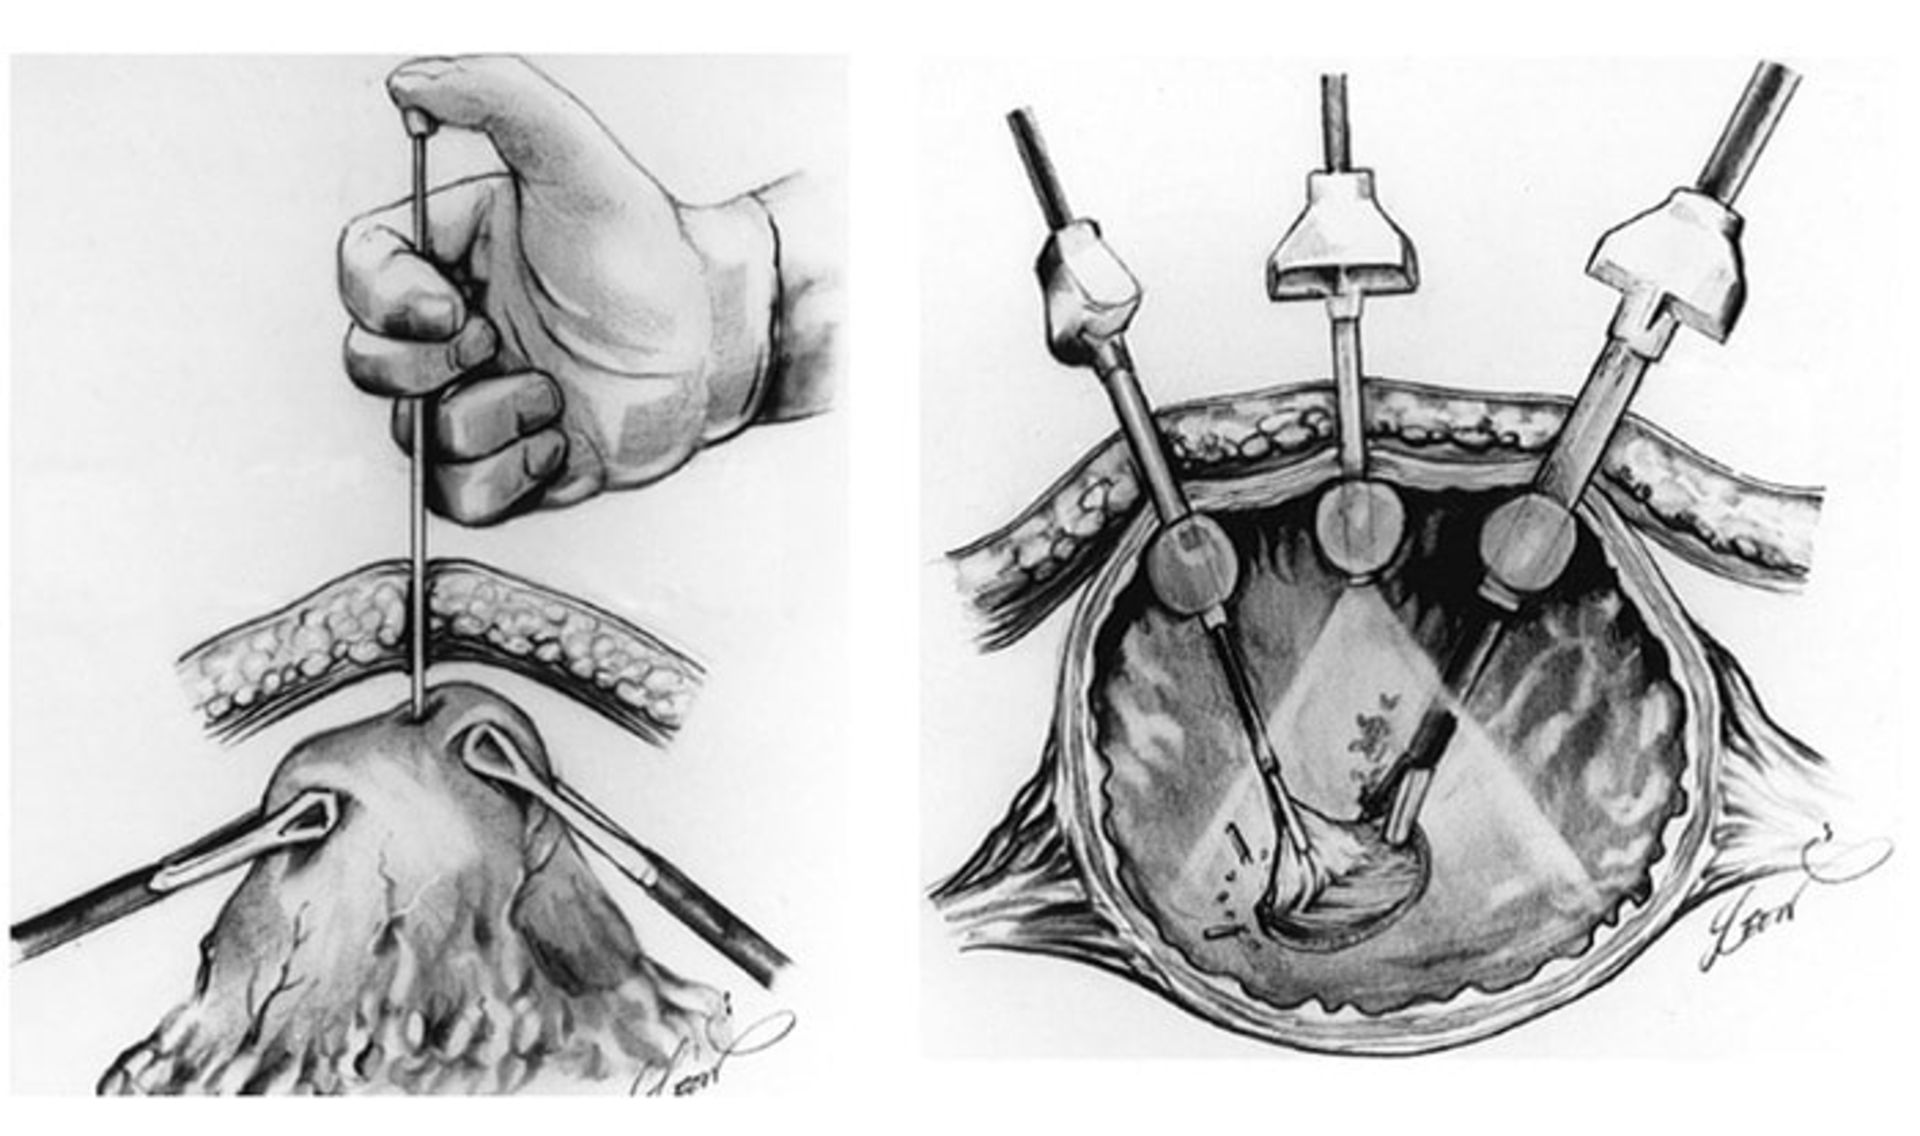

لاپاراسکوپی: از این روش معمولا زمانیکه سرطان معده تشخیص داده شده باشد، استفاده میشود. اگرچه سیتیاسکن یا MRI میتوانند تصاویر دقیقی از داخل بدن ایجاد کنند، ولی ممکن است نتوانند تومورهای خیلی کوچک را نشان دهند. پزشکان ممکن است قبل از انجام عمل جراحی برای تأیید وجود سرطان در معده و قابل برداشت بودن آن، عمل لاپاراسکوپی را انجام دهند. این عمل در یک اتاق عمل و تحت بیهوشی عمومی انجام میشود. یک لاپاراسکوپ (یک لولهی نازک انعطافپذیر) ازطریق منفذی کوچک در پهلوی بیمار وارد بدن او میشود. لاپاراسکوپ دارای یک دوربین ویدئویی کوچک در انتهای خود است که تصاویر داخل شکم را به یک صفحهی نمایش میفرستد.

با استفاده از این روش پزشکان میتوانند به سطوح اندامها و گرههای لنفاوی مجاور نگاه نزدیکتری بیندازند یا حتی نمونههای کوچکی نیز بگیرند. اگر انتشار سرطان به چشم نیاید، گاهی پزشکان شکم را با استفاده از محلول نمکی شستشو میدهند. این مایع سپس برداشته میشود و برای بررسی حضور احتمالی سلولهای سرطانی مورد بررسی قرار میگیرد. اگر چنین باشد، به این معنا است که سرطان منتشر شده حتی اگر انتشار آن قابلمشاهده نباشد. گاهی نیز عمل لاپاراسکوپی با اولتراسوند ترکیب میشود تا تصویر بهتری از سرطان فراهم شود.

اغلب جراحیهای معده کلی و جرئی ازطریق ایجاد یک شکاف بزرگ در پوست شکم انجام میشوند. این عمل در برخی از مراکز پزشکی با استفاده از لاپاراسکوپی انجام میشود.